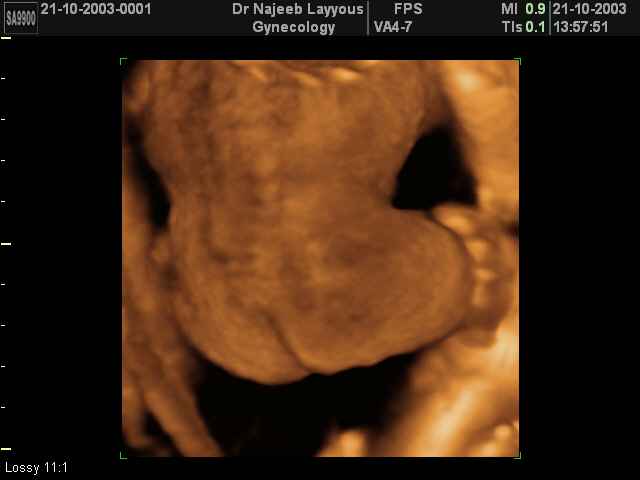

- لقطات فيديو للجنين بجهاز الموجات فوق صوتية رباعي الأبعاد

- صور للجنين في المراحل الأولى من الحمل

صور لأعضاء الجنين بجهاز الموجات فوق صوتية ثلاثي الأبعاد | الدكتور نجيب ليوس